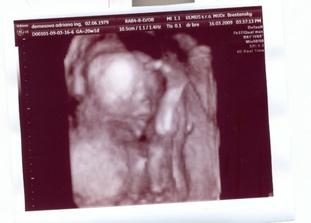

Teraz nás už konečne čaká 3Dčko v pondelok....a hádam budeme vidieť aj čiaročku alebo paličku.

16.3.2009 3D: 20tt+1, a je to tam! čiaročka!!! takže vraj na milión % bude dievčatko. s taťuldom sa neskutočne tešíme na našu bambuľku!